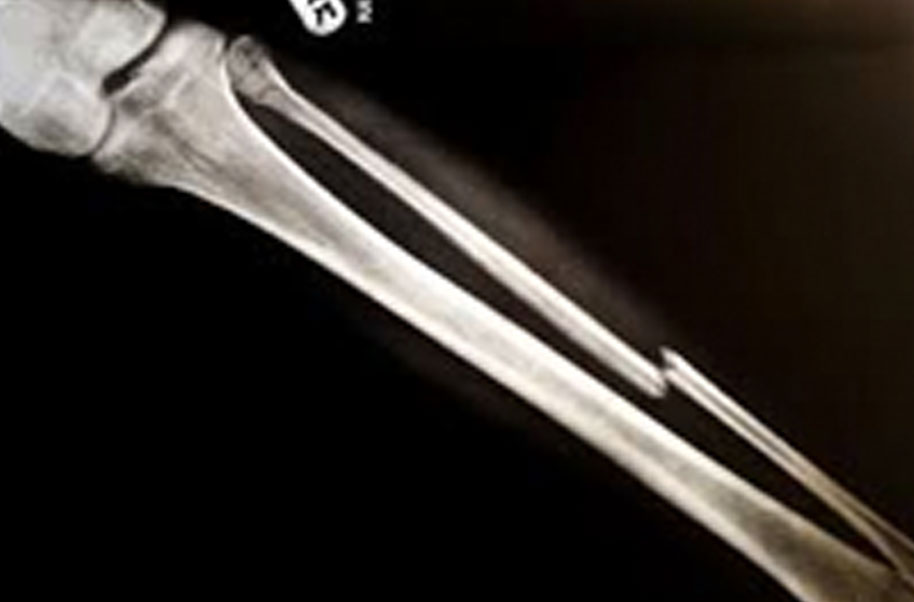

Metacarpel (Broken Bone)

A complete or partial break in a bone.

- Treatment often involves resetting the bone in place and immobilising it in a cast or splint to give it time to heal. Sometimes, surgery with rods, plates and screws may be required.

Causes of bone fractures include trauma, overuse and diseases that weaken bones.